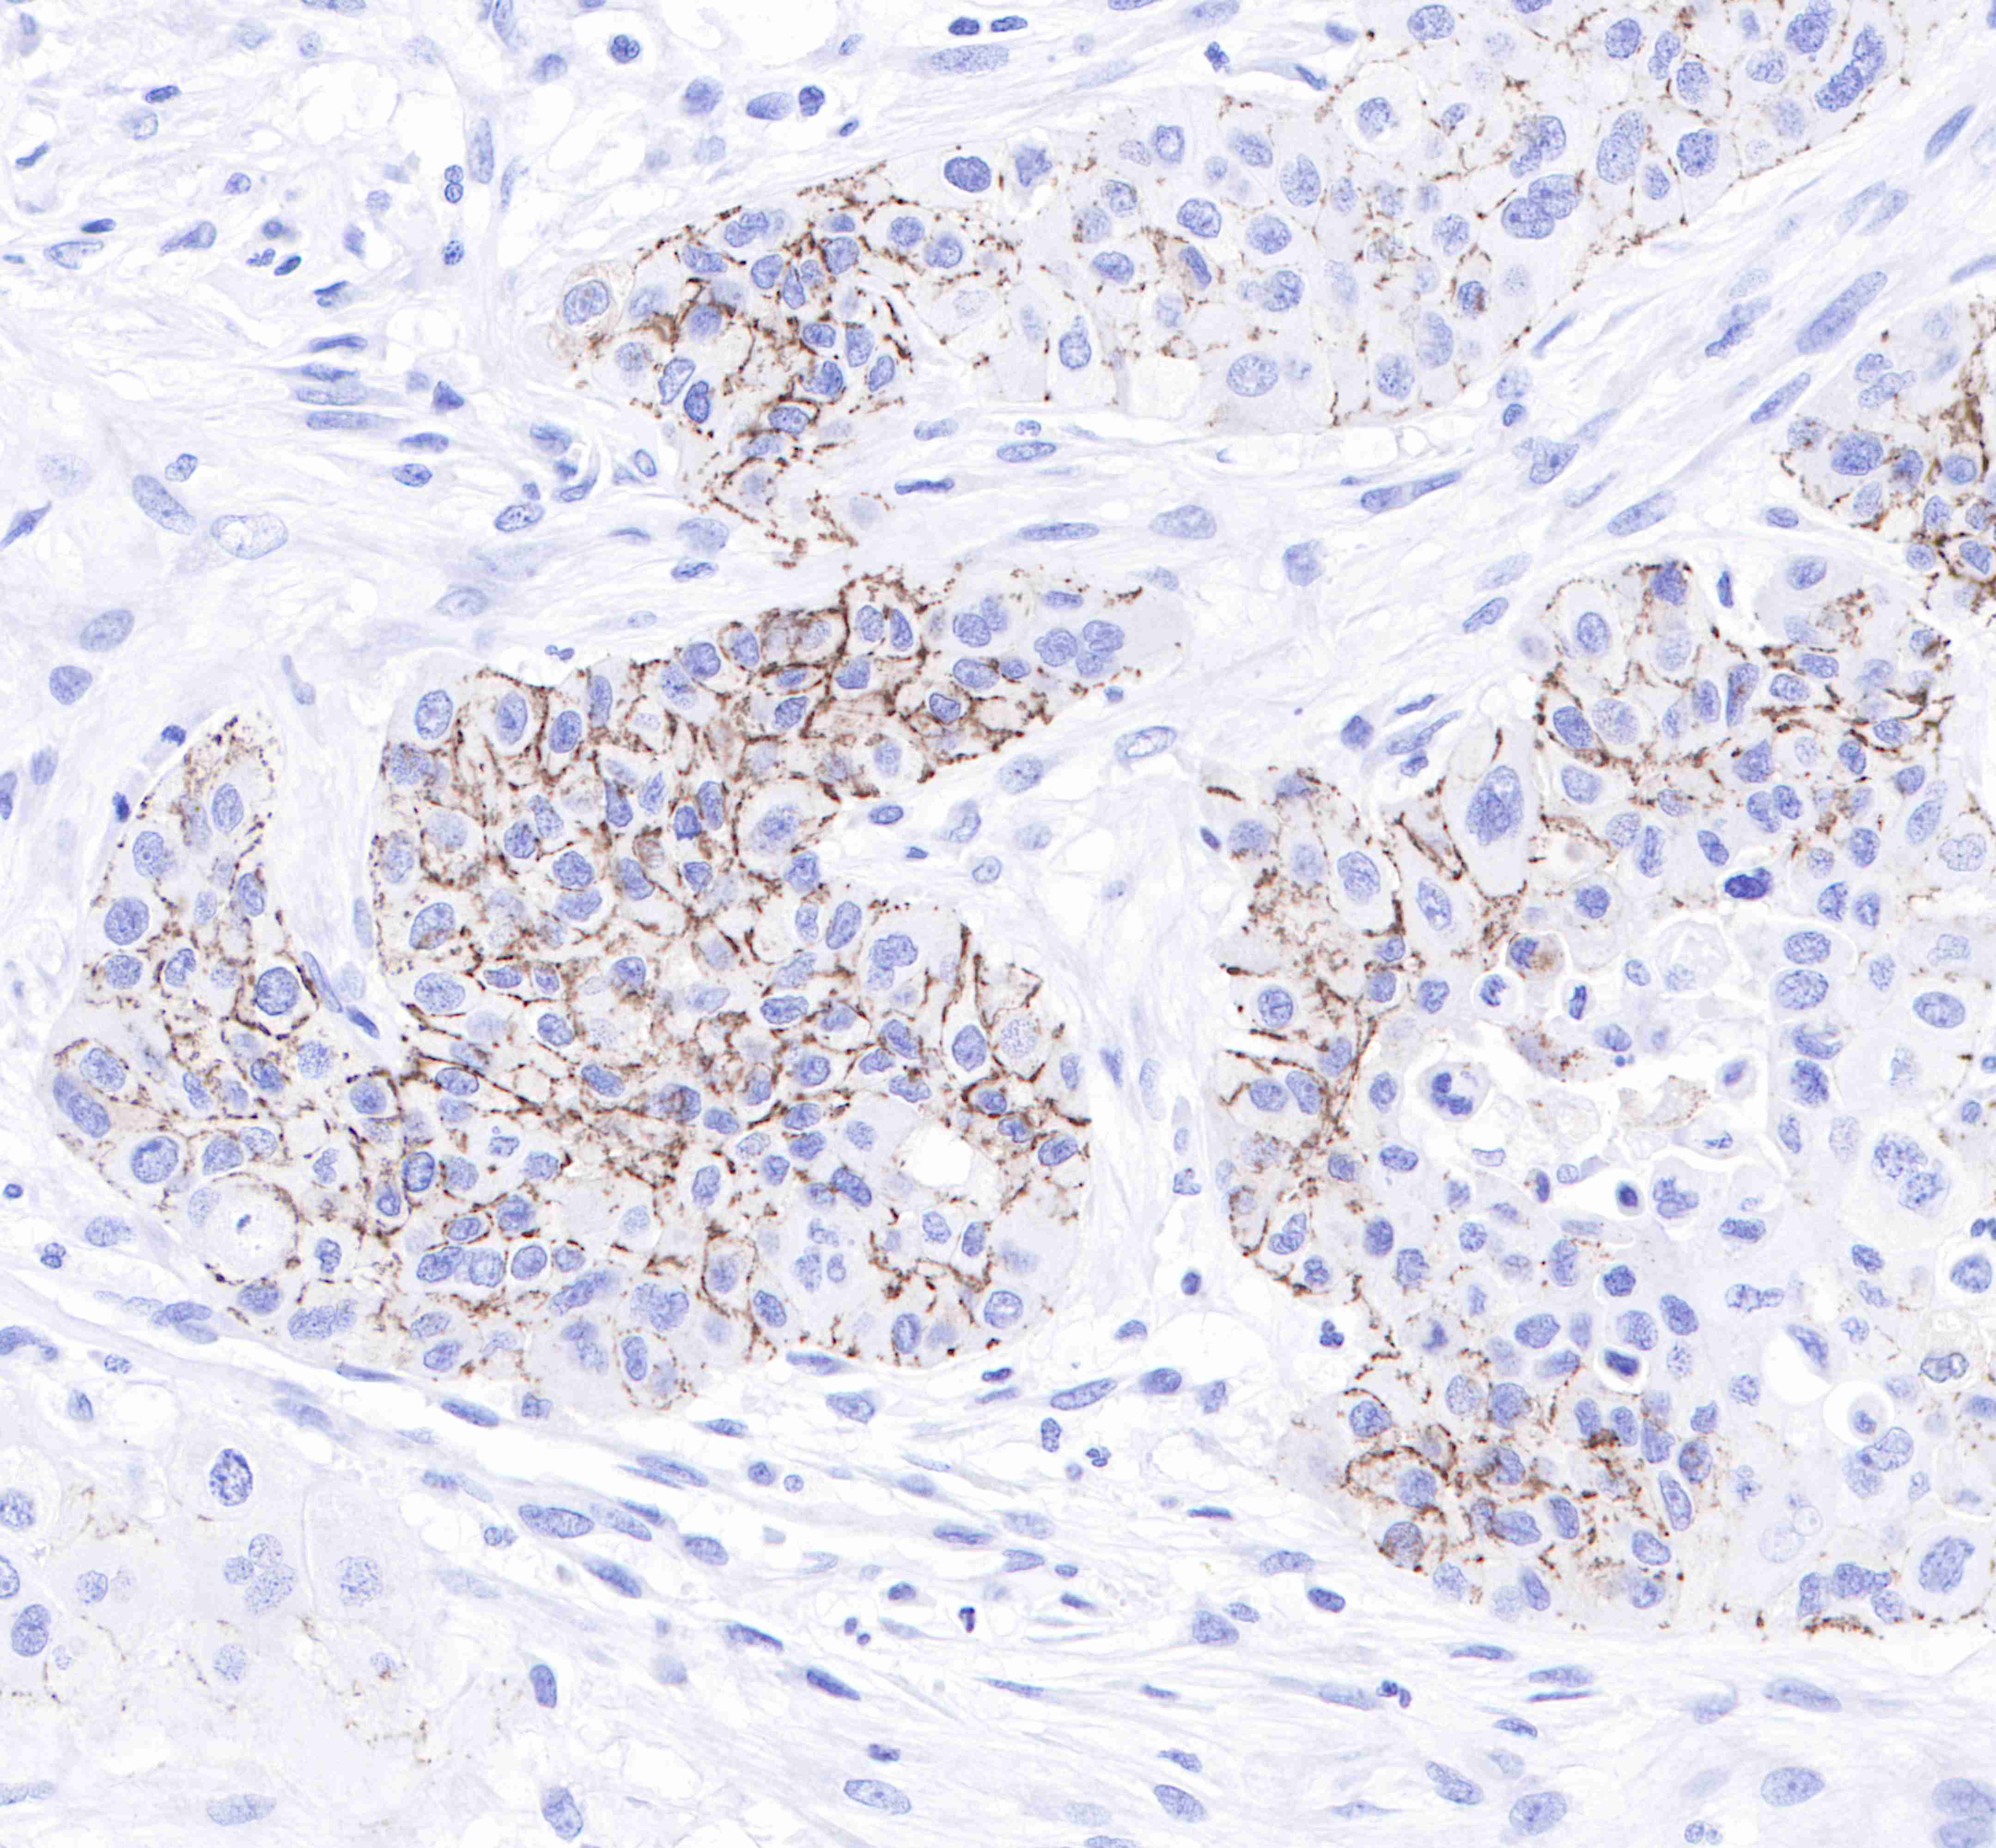

| IHC-P |

1:250 |

Claudin-1 is a protein that in humans is encoded by the CLDN1 gene.It belongs to the group of claudins.

Tight junctions represent one mode of cell-to-cell adhesion in epithelial or endothelial cell sheets, forming continuous seals around cells and serving as a physical barrier to prevent solutes and water from passing freely through the paracellular space. These junctions are composed of sets of continuous networking strands in the outwardly facing cytoplasmic leaflet, with complementary grooves in the inwardly facing extracytoplasmic leaflet. The protein encoded by this gene, a member of the claudin family, is an integral membrane protein and a component of tight junction strands. Loss of function mutations result in neonatal ichthyosis-sclerosing cholangitis syndrome.